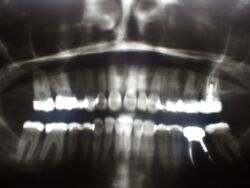

Patientin aus Berlin zur Kontrolle der Okklusion

Gemessen am Umfang der Versorgung sind die Okklusionskorrekturen gering, die Patientin aber auch sehr okklusionssensibel.

Deshalb werden umfangreiche Kontrollen der statischen und der dynamischen Okkluson durchgeführt und vorrangigt das notwendige Spiel georüft und im Bereich weniger Mikrometer eingestellt, dass die Bisslage eines CMD Patienten benötigt.